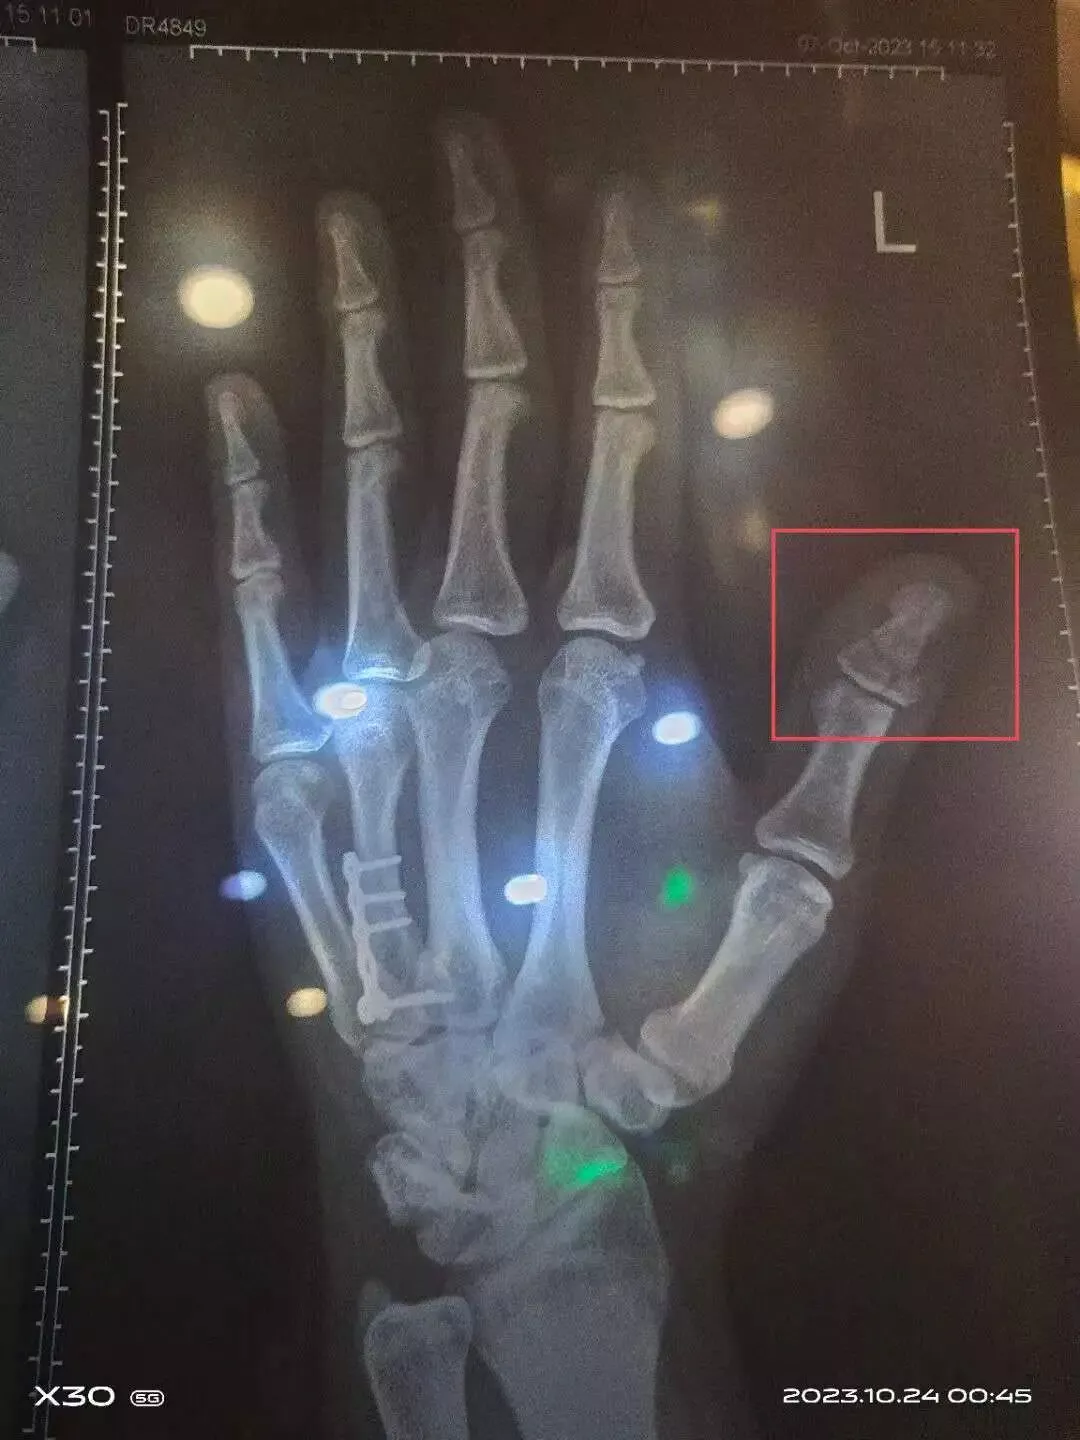

X光片显示,杜北的左手大拇指发生了粉碎性骨折,有明显移位,双膝大面积软组织挫伤。医生建议做手术住院治疗,用钢钉把大拇指穿起来、固定住。

杜光左手X光片,显示其左手大拇指存在粉碎性骨折。(图_受访者提供)